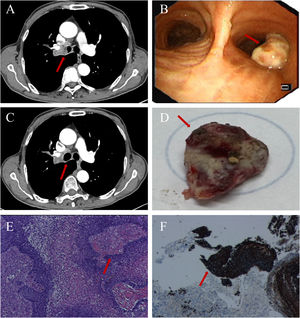

A 75-year-old man presented with cough. Thoracic computed tomography (CT) performed on October 15th, 2025, revealed a mass causing luminal obstruction of the right main bronchus (Fig. 1A, arrow). Subsequent bronchoscopy on October 24th, 2025, demonstrated a corresponding endobronchial neoplasm at the same site (Fig. 1B, arrow). On November 7th, 2025, the patient spontaneously expectorated a 2.5cm×2.0cm×1.0cm tissue fragment (Fig. 1D), after which he reported marked improvement in respiratory symptoms. Follow-up CT on November 9th, 2025, showed restoration of bronchial lumen patency at the previously obstructed site, with only minor, self-limited hemorrhage (Fig. 1C, arrow). Histopathological examination of the expectorated specimen on November 11th, 2025, confirmed the diagnosis of squamous cell carcinoma (Fig. 1E and F).

Thoracic CT section (A) showing obstruction of the right main bronchus (arrow). Flexible bronchoscopy (B) reveals an endobronchial neoplasm at the corresponding site (arrow). Follow-up thoracic CT (C) demonstrates restored patency of the previously obstructed bronchial lumen (arrow). Macroscopic view of the spontaneously expectorated tissue mass (D) (arrow). Histopathological examination (E) and immunohistochemical staining (F) confirm the diagnosis of squamous cell carcinoma (arrows).